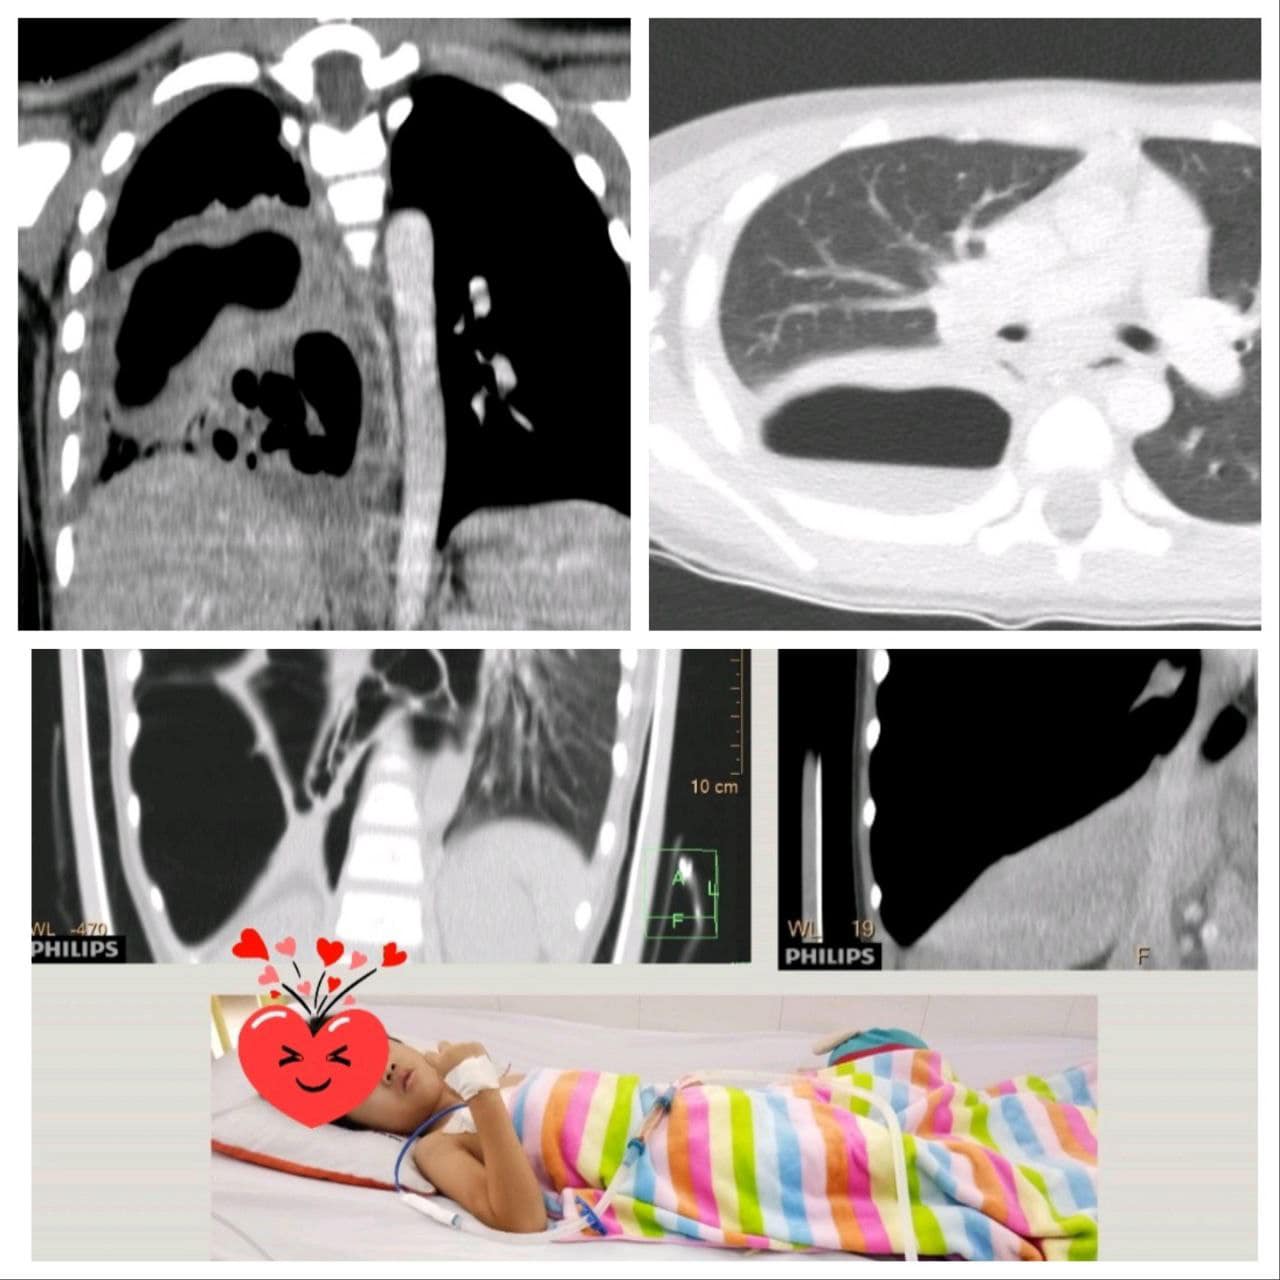

រាជធានីភ្នំពេញ៖ នៅថ្ងៃទី២៧ ខែកុម្ភៈ ឆ្នាំ២០២៣ នៅចុងសប្តាហ៍កន្លងមកនេះមន្ទីរពេទ្យគន្ធបុប្ជាបានអោយដឹងថា មានកុមារាតូចអាយុ៥ឆ្នាំ មកពីគ្លីនិកឯកជនមួយនៅភ្នំពេញ មានជំងឺរលាកសួតក្លាយជាបូសសួតនិងធ្លាយថង់សួតយ៉ាងធ្ងន់ធ្ងរបំផុត។

កូនតូច ត្រូវបានជួយសង្គ្រោះជីវិតនៅមន្ទីរពេទ្យគន្ធបុប្ផាភ្នំពេញ។ ក្រោយការព្យាបាលនិងចោះបង្ហូរខ្ទុះក្នុងសួត និងថែទាំព្យាបាលអស់២៥ថ្ងៃ ដោយក្រុមគ្រូពេទ្យឯកទេសសង្គ្រោះបន្ទាន់នៃមន្ទីរពេទ្យគន្ធបុប្ផាភ្នំពេញបានសង្គ្រោះជីវិតមួយនេះ។ រាល់ការព្យាបាលទាំងអស់គឺឥតគិតថ្លៃសម្រាប់គ្រប់ៗគ្នា ដោយគ្មានការរើសអើង ៕